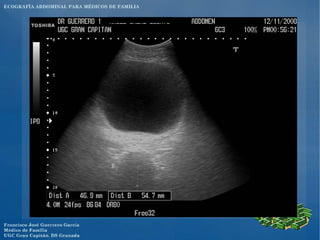

El documento presenta un programa de ecografía abdominal para médicos de familia que incluye presentaciones sobre generalidades de la ecografía y anatomía normal de los órganos abdominales los jueves, y sobre imágenes anormales en ecografía abdominal y ecografía obstétrica los viernes, con un caso clínico el sábado en el centro.